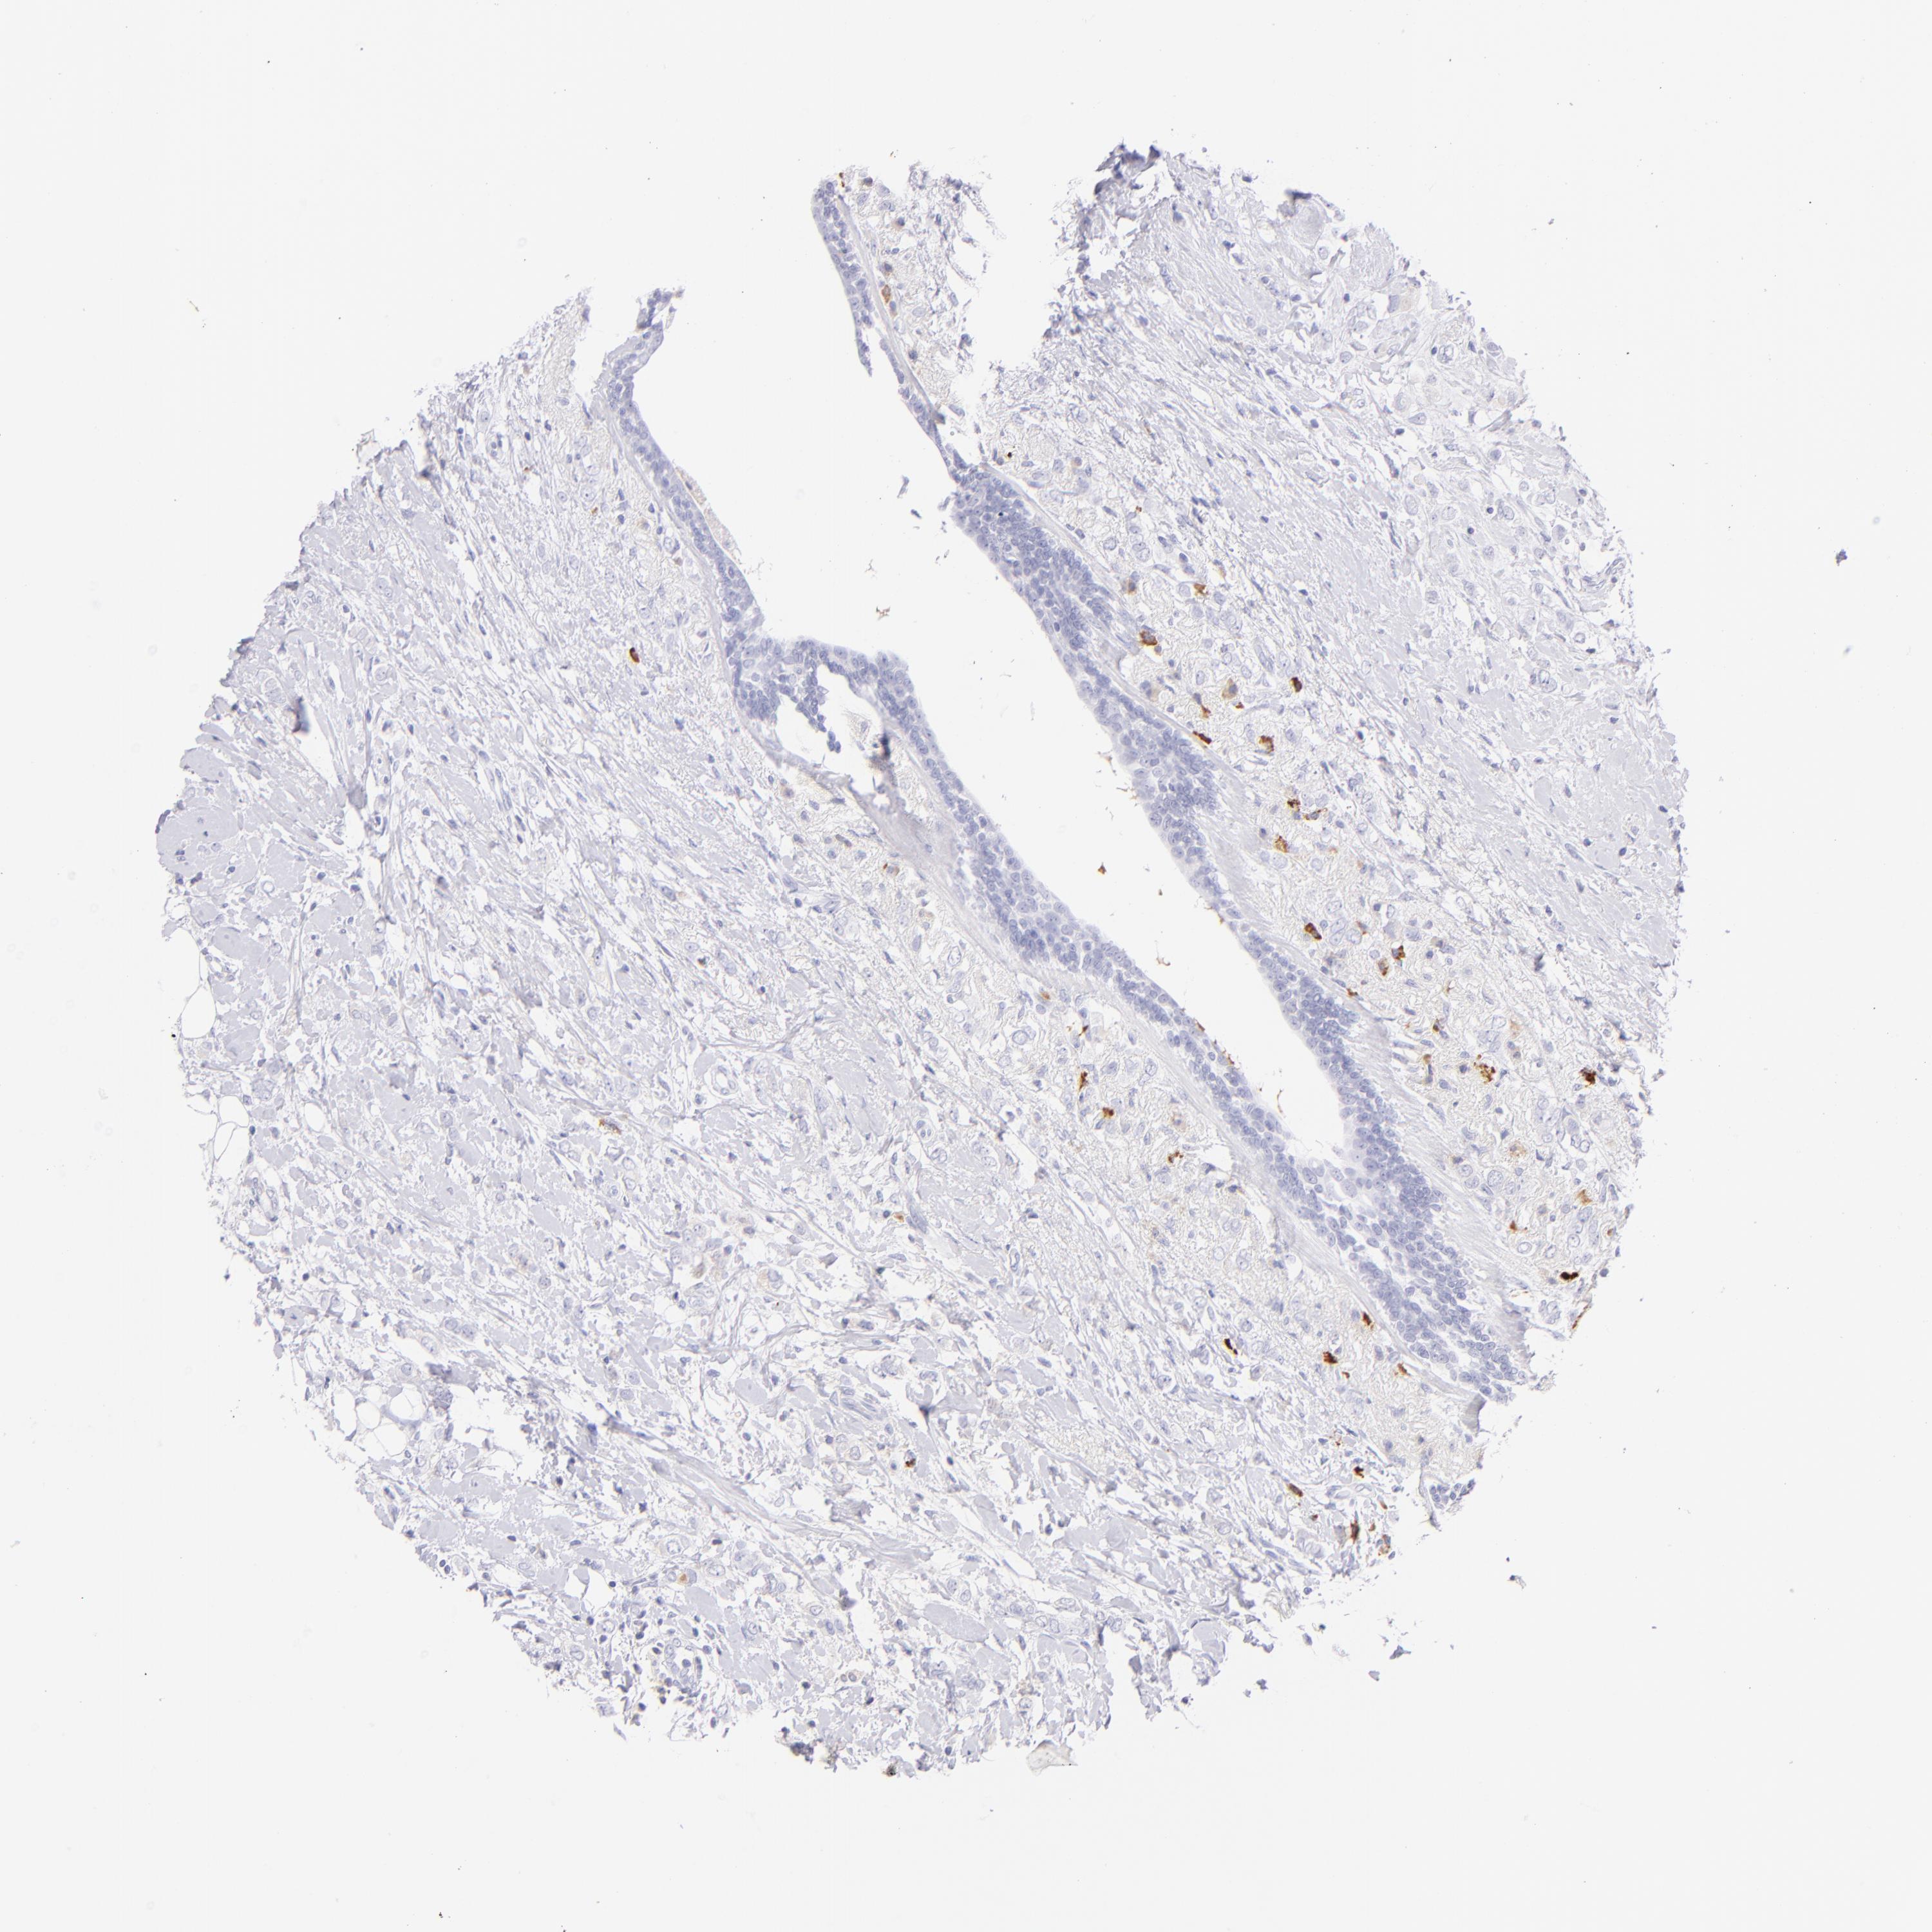

BRCA TCGA BRCA VALIDATION PROTEIN EXPRESSION

ANTIBODIES

AND

VALIDATION